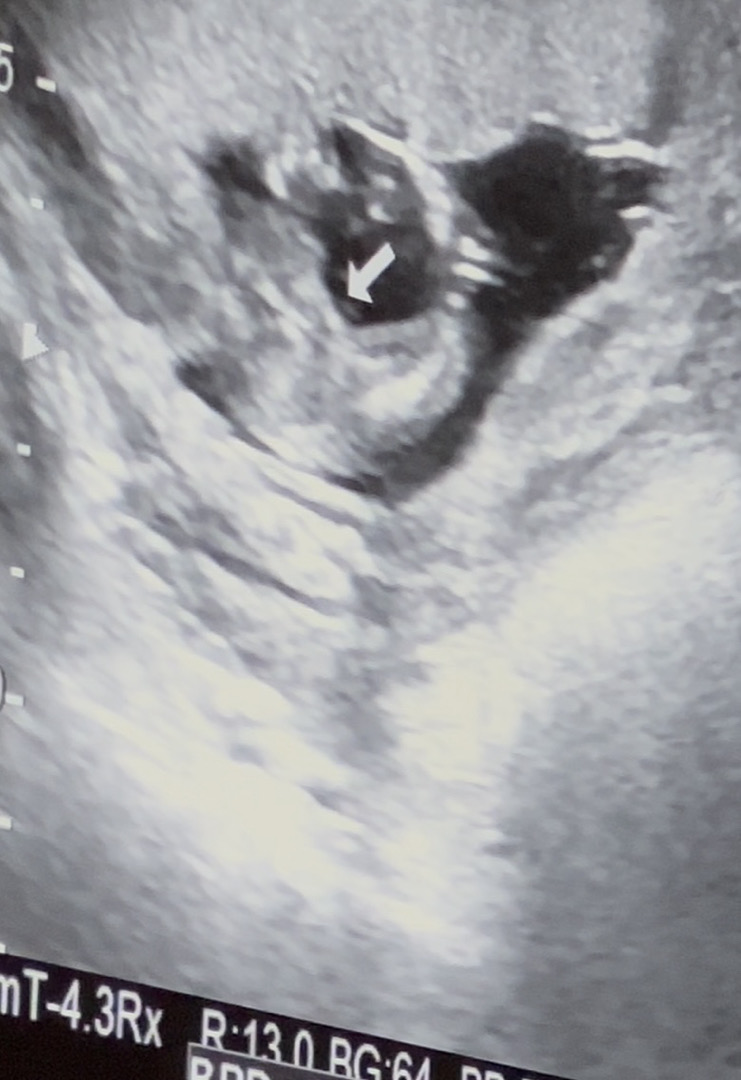

14주5일 이정도 밋밋하면 여자아이 일까요

14주5일차입니다! 선생님이 아직 확정짓긴 이르지만 밋밋한걸로봐서 여자아이 일것같다고 하시는데 제가 보기엔 여자아이 맞을꺼같은데 여러분이 보시기에 어떠신가요?! ㅎ